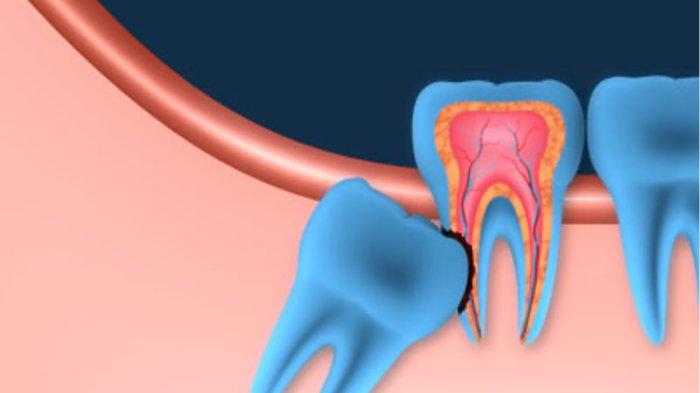

Gigi bungsu yang tumbuh miring berisiko merusak gigi sebelahnya, serta menyebabkan kerusakan saraf dan tulang rahang.

Secara umum, impaksi pada gigi bungsu disebabkan karena ruang di dalam rahang tidak cukup untuk gigi tumbuh secara normal.